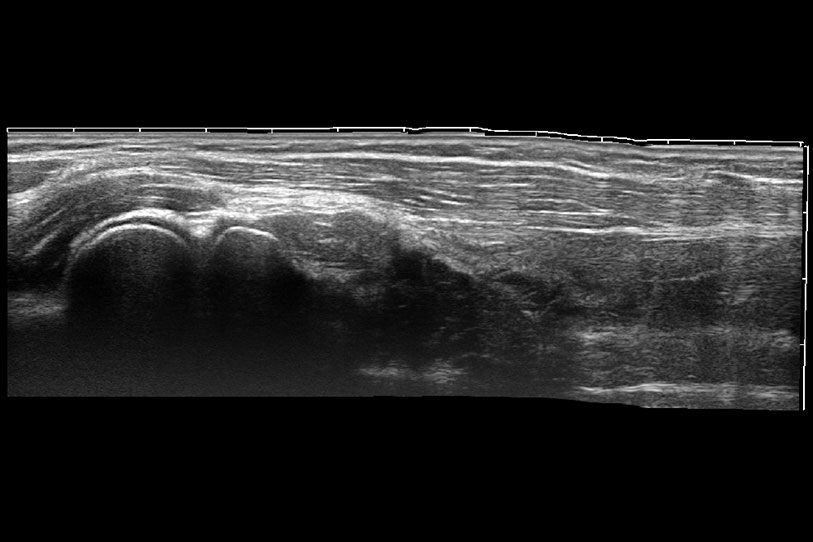

大型犬、馬科、農(nóng)場動(dòng)物及大型異寵動(dòng)物

通過色彩血流和實(shí)時(shí)寬景相結(jié)合,可觀察到完整的靜脈或動(dòng)脈的血流,方便醫(yī)生檢查。實(shí)時(shí)掃查過程中,如有任何操作失誤也可以很容易地進(jìn)行回掃擦除,而不會中斷掃查。